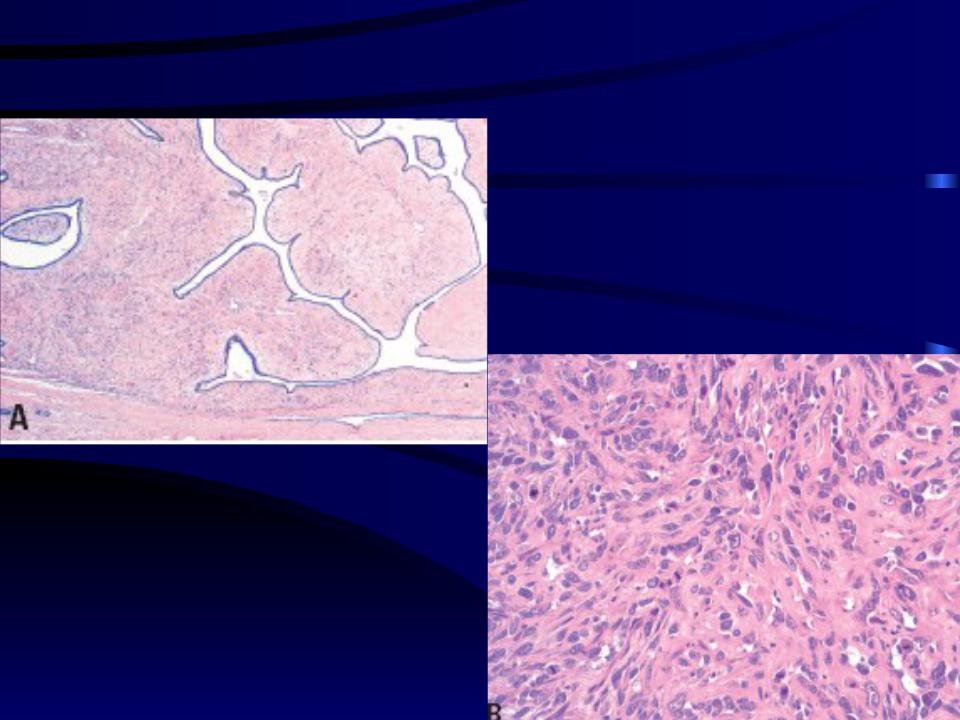

Раздел: Снимки-откровения